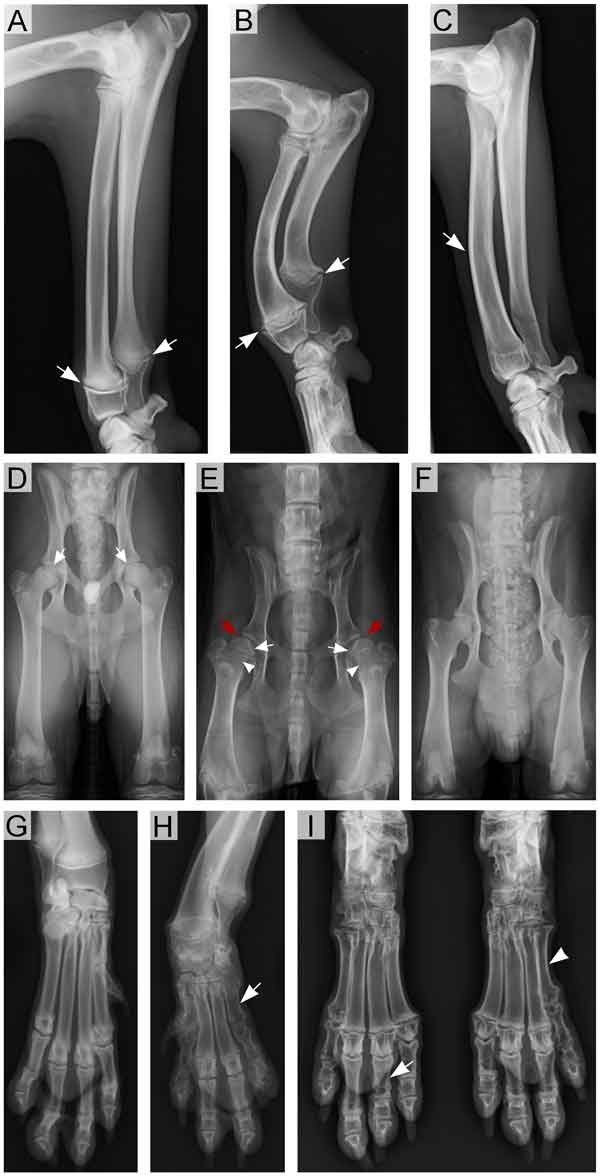

La mutación ITGA10, autosómica recesiva, causa un desproporcionado enanismo y alteraciones en la estatura de diversa gravedad. La apariencia de los perros afectados se caracteriza por extremidades considerablemente más cortas que las de los perros normales. Otras anomalías esqueléticas pueden acompañar a estas deformidades, incluyendo antebrazos arqueadas, dedos anormales, y cabezas femorales malformadas.

Los códigos de los genes ITGA10 ensamblan en un receptor de colágeno específico del cartílago que se encuentra en las placas de crecimiento de los huesos largos. El receptor es muy importante para el proceso de osificación endocondral, en el que las células de cartílago proliferan primero, y entonces se reemplazan por el tejido óseo. En consecuencia, se han encontrado varias anomalías en las placas de crecimiento de los perros afectados tanto en exámenes radiográficos como histológicos.